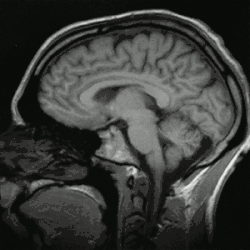

Cérebro humano é o órgão central do sistema nervoso humano e, com a medula espinhal, forma o sistema nervoso central. [2] O encéfalo consiste no cérebro, no tronco cerebral e no cerebelo. [3]O cérebro controla a maioria das atividades do corpo, ao mesmo tempo em que processa, integra e coordena as informações que recebe do sistema sensorial e toma decisões quanto às instruções enviadas ao resto do corpo. O órgão, que está contido e protegido pelos ossos do crânio da cabeça e é a maior parte do encéfalo humano, consiste em dois hemisférios cerebrais. Cada hemisfério possui um núcleo interno composto de matéria branca e uma superfície externa - o córtex cerebral - composto de matéria cinzenta. O córtex tem uma camada externa, o neocórtex e um alocórtex interno. O neocórtex é formado por seis camadas neuronais, enquanto o alocórtex tem três ou quatro. Cada hemisfério é convencionalmente dividido em quatro lobos cerebrais - frontal, temporal, parietal e occipital, [2] há também os lobos insulares, que se localizam em uma dobra mais profunda do telencéfalo. [4] O lobo frontal está associado às funções executivas, como autocontrole, planejamento, raciocínio e pensamento abstrato, enquanto o lobo occipital é dedicado à visão. [5]Dentro de cada lobo, áreas corticais estão associadas a funções específicas, como as regiões sensoriais, motoras e de associação. Embora os hemisférios esquerdo e direito sejam bastante semelhantes em forma e função, algumas funções estão associadas especificamente a um lado, como a linguagem à esquerda e a habilidade visual-espacial à direita. Os hemisférios são conectados por tratos nervosos comissurais, sendo o maior o corpo caloso.

O tronco cerebral consiste no mesencéfalo, na ponte e no bulbo raquidiano. O cerebelo está conectado ao tronco cerebral por três pares de tratos nervosos chamados pedúnculos cerebelares. Dentro do cérebro está o sistema ventricular, que consiste em quatro ventrículos interconectados nos quais o líquido cefalorraquidiano é produzido e circulado. Abaixo do córtex cerebral existem várias estruturas importantes, incluindo o tálamo, o epitálamo, a glândula pineal, o hipotálamo, a glândula pituitária e o subtálamo; as estruturas límbicas, incluindo a amígdala e o hipocampo; o claustro, os vários núcleos dos gânglios da base; as estruturas basais do prosencéfalo e os três órgãos circunventriculares. As células do cérebro incluem neurônios e gliocitos. Existem mais de 86 bilhões de neurônios no cérebro e um número mais ou menos igual de outras células. [2] A atividade cerebral é possibilitada pelas interconexões de neurônios e sua liberação de neurotransmissores em resposta aos impulsos nervosos. Os neurônios se conectam para formar caminhos neurais, circuitos neurais e sistemas de rede elaborados. Todo o circuito é impulsionado pelo processo de neurotransmissão.

Córtex cerebral

No cérebro há uma distinção visível entre a chamada massa cinzenta e a massa branca, constituída pelas fibras (axónios) que interligam os neurónios. A substância cinzenta do cérebro, o córtex cerebral, é constituído de corpos celulares de dois tipos de células: as células de Glia - também chamadas de neuróglias - e os neurônios. O córtex cerebral humano é um tecido fino (como uma membrana) que tem uma espessura entre 1 e 4 mm e uma estrutura laminar formada por 6 camadas distintas de diferentes tipos de corpos celulares de neurônios. Perpendicularmente às camadas, existem grandes neurônios chamados neurônios piramidais que ligam as várias camadas entre si e representam cerca de 85% dos neurônios no córtex. Os neurônios piramidais estão interligados uns aos outros através de ligações excitatórias e pensa-se que a sua rede é o "esqueleto" da organização cortical. Podem receber entradas de milhares de outros neurônios e podem transmitir sinais a distâncias da ordem dos centímetros e atravessando várias camadas do córtex. Os estudos realizados indicam que cada célula piramidal está ligada a quase tantas outras células piramidais quantas as suas sinapses (cerca de 4 mil); o que implica que nenhum neurônio está a mais de um número pequeno de sinapses de distância de qualquer outro neurônio no córtex.

Embora até há poucos anos se pensasse que a função das células de Glia é essencialmente a de nutrir, isolar e proteger os neurônios, estudos mais recentes sugerem que os astrócitos podem ser tão críticos para certas funções corticais quanto os neurônios. As diferentes partes do córtex cerebral são divididas em quatro áreas chamadas de lobos cerebrais, tendo cada uma funções diferenciadas e especializadas. Os lobos cerebrais são designados pelos nomes dos ossos cranianos nas suas proximidades e que os recobrem. O lobo frontal fica localizado na região da testa; o lobo occipital, na região da nuca; o lobo parietal, na parte superior central da cabeça; e os lobos temporais, nas regiões laterais da cabeça, por cima das orelhas.